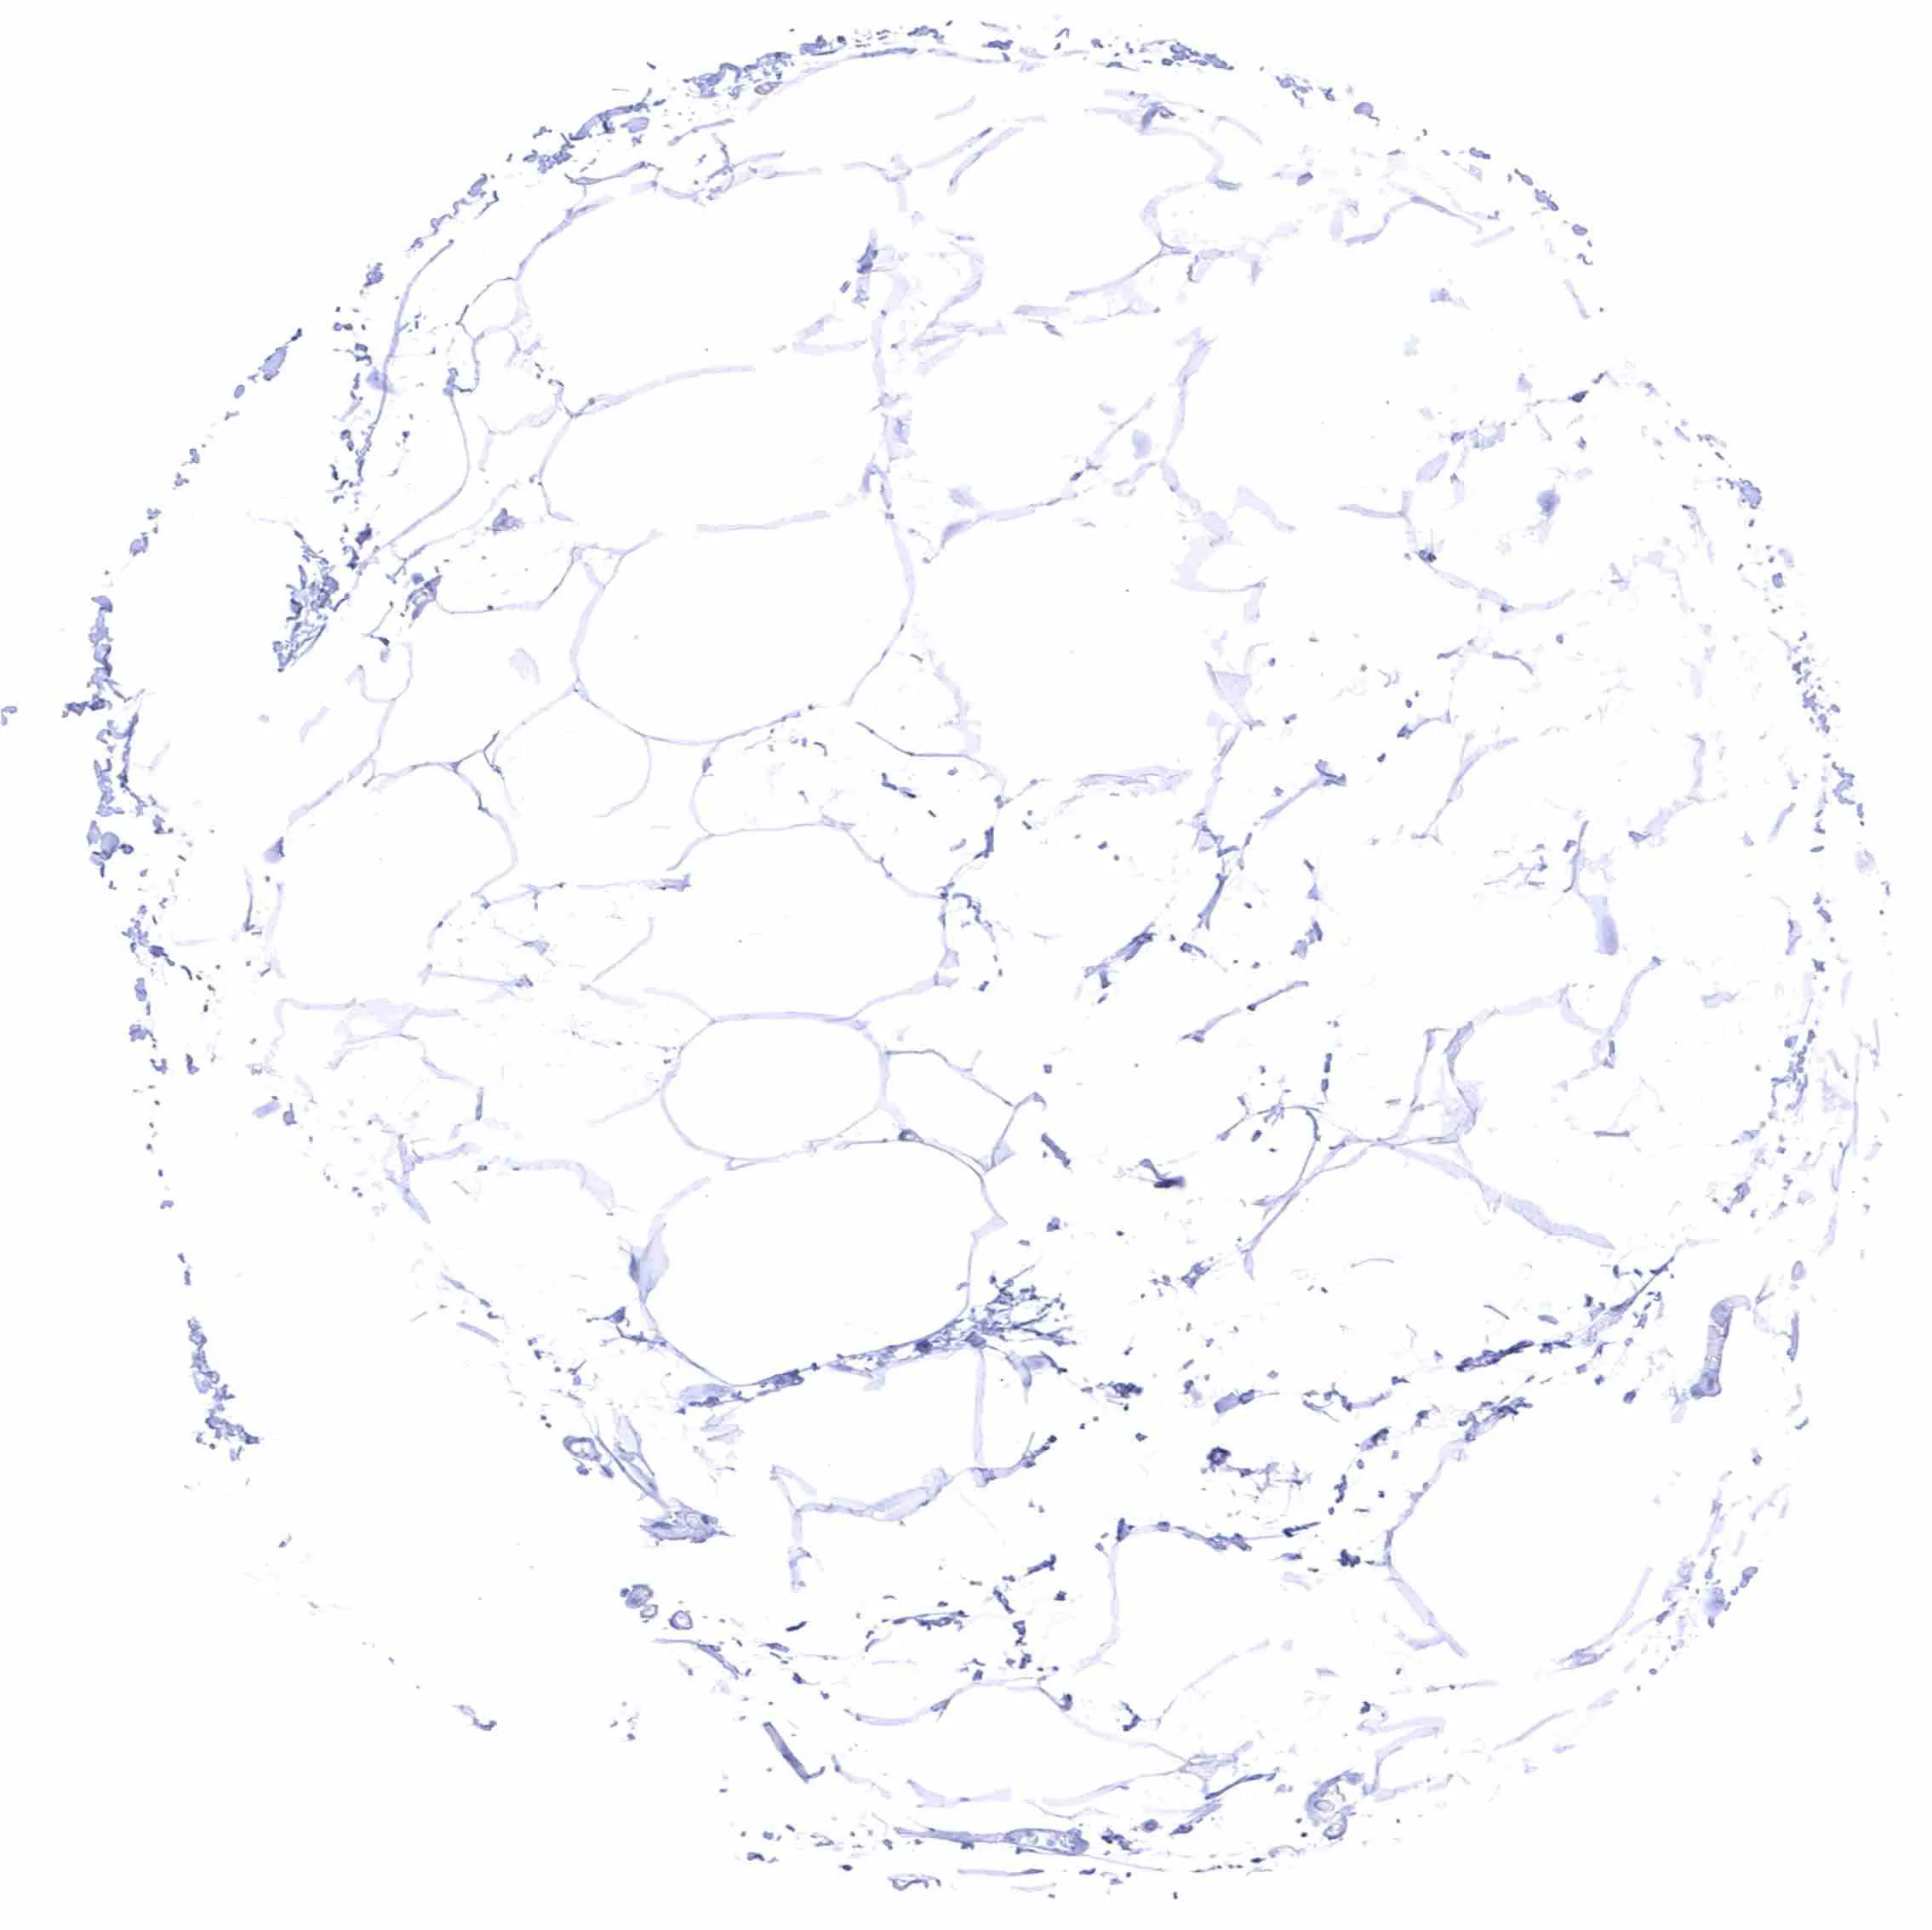

Fat